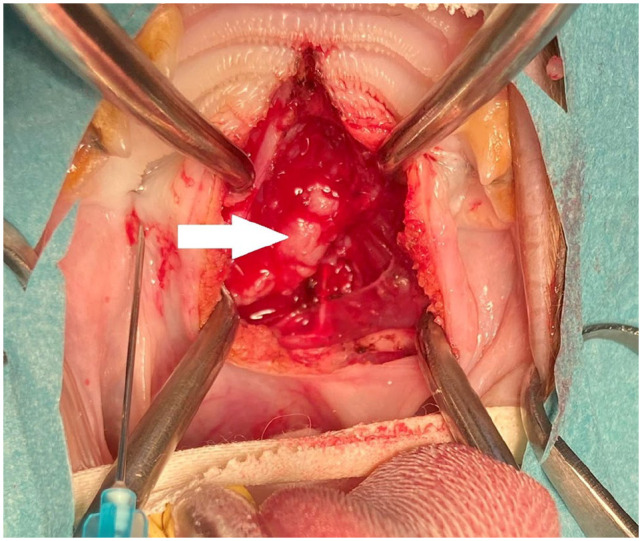

Case summary: A 10-year-old castrated male crossbreed Birman cat was presented for respiratory difficulties, nasal discharge, dysphagia and wheezing. An obstructive nasopharyngeal mass invading the caudoventral nasal cavity and the left sphenoid sinus was observed on a CT scan. Surgical treatment via a ventral rhinotomy and curettage was performed. Histopathology revealed an adenocarcinoma with tubulotrabecular architecture. The cat's clinical signs significantly improved postoperatively. After 10 months, a recurrence was documented and a second surgical procedure was performed that allowed the patient to live an additional 6 months without clinical signs and an overall survival time of 19 months after first presentation.

Relevance and novel information: This case report describes a nasopharyngeal adenocarcinoma treated by ventral rhinotomy in a cat. To our knowledge, there is only one other report describing this surgery on a nasal adenocarcinoma in a cat. The tomodensitometric, endoscopic and unusual histological appearance of the mass are reported. The prognosis after surgical removal of nasal adenocarcinomas in cats is only sparsely documented. This case demonstrates that ventral rhinotomy might be considered if first-line treatment is declined.